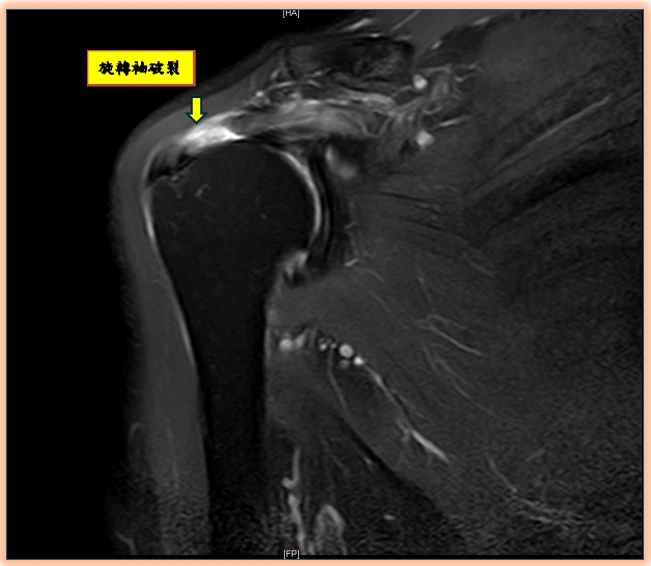

旋轉肌袖破裂如何診斷?陳昱彰表示,起初常被誤認為肌腱拉傷或五十肩,但症狀久未改善時,應盡早請骨科醫師進行正確診斷與治療。診斷方式除理學檢查、X光、超音波外,也常以核磁共振(MRI)確認破裂程度與型態,作為手術規劃依據。

image

旋轉肌袖破裂常被認為五十肩,建議有相關症狀及早就醫治療。(圖片來源:台北市立聯合醫院)